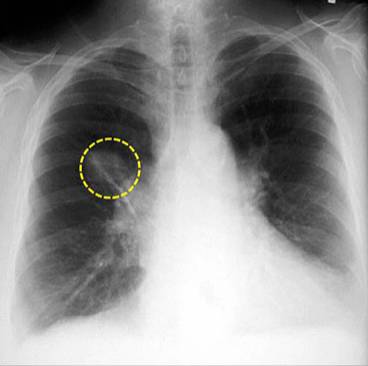

胸部x線必讀 15個容易忽視但重要的表現 醫學界急診與重症頻道 微文庫